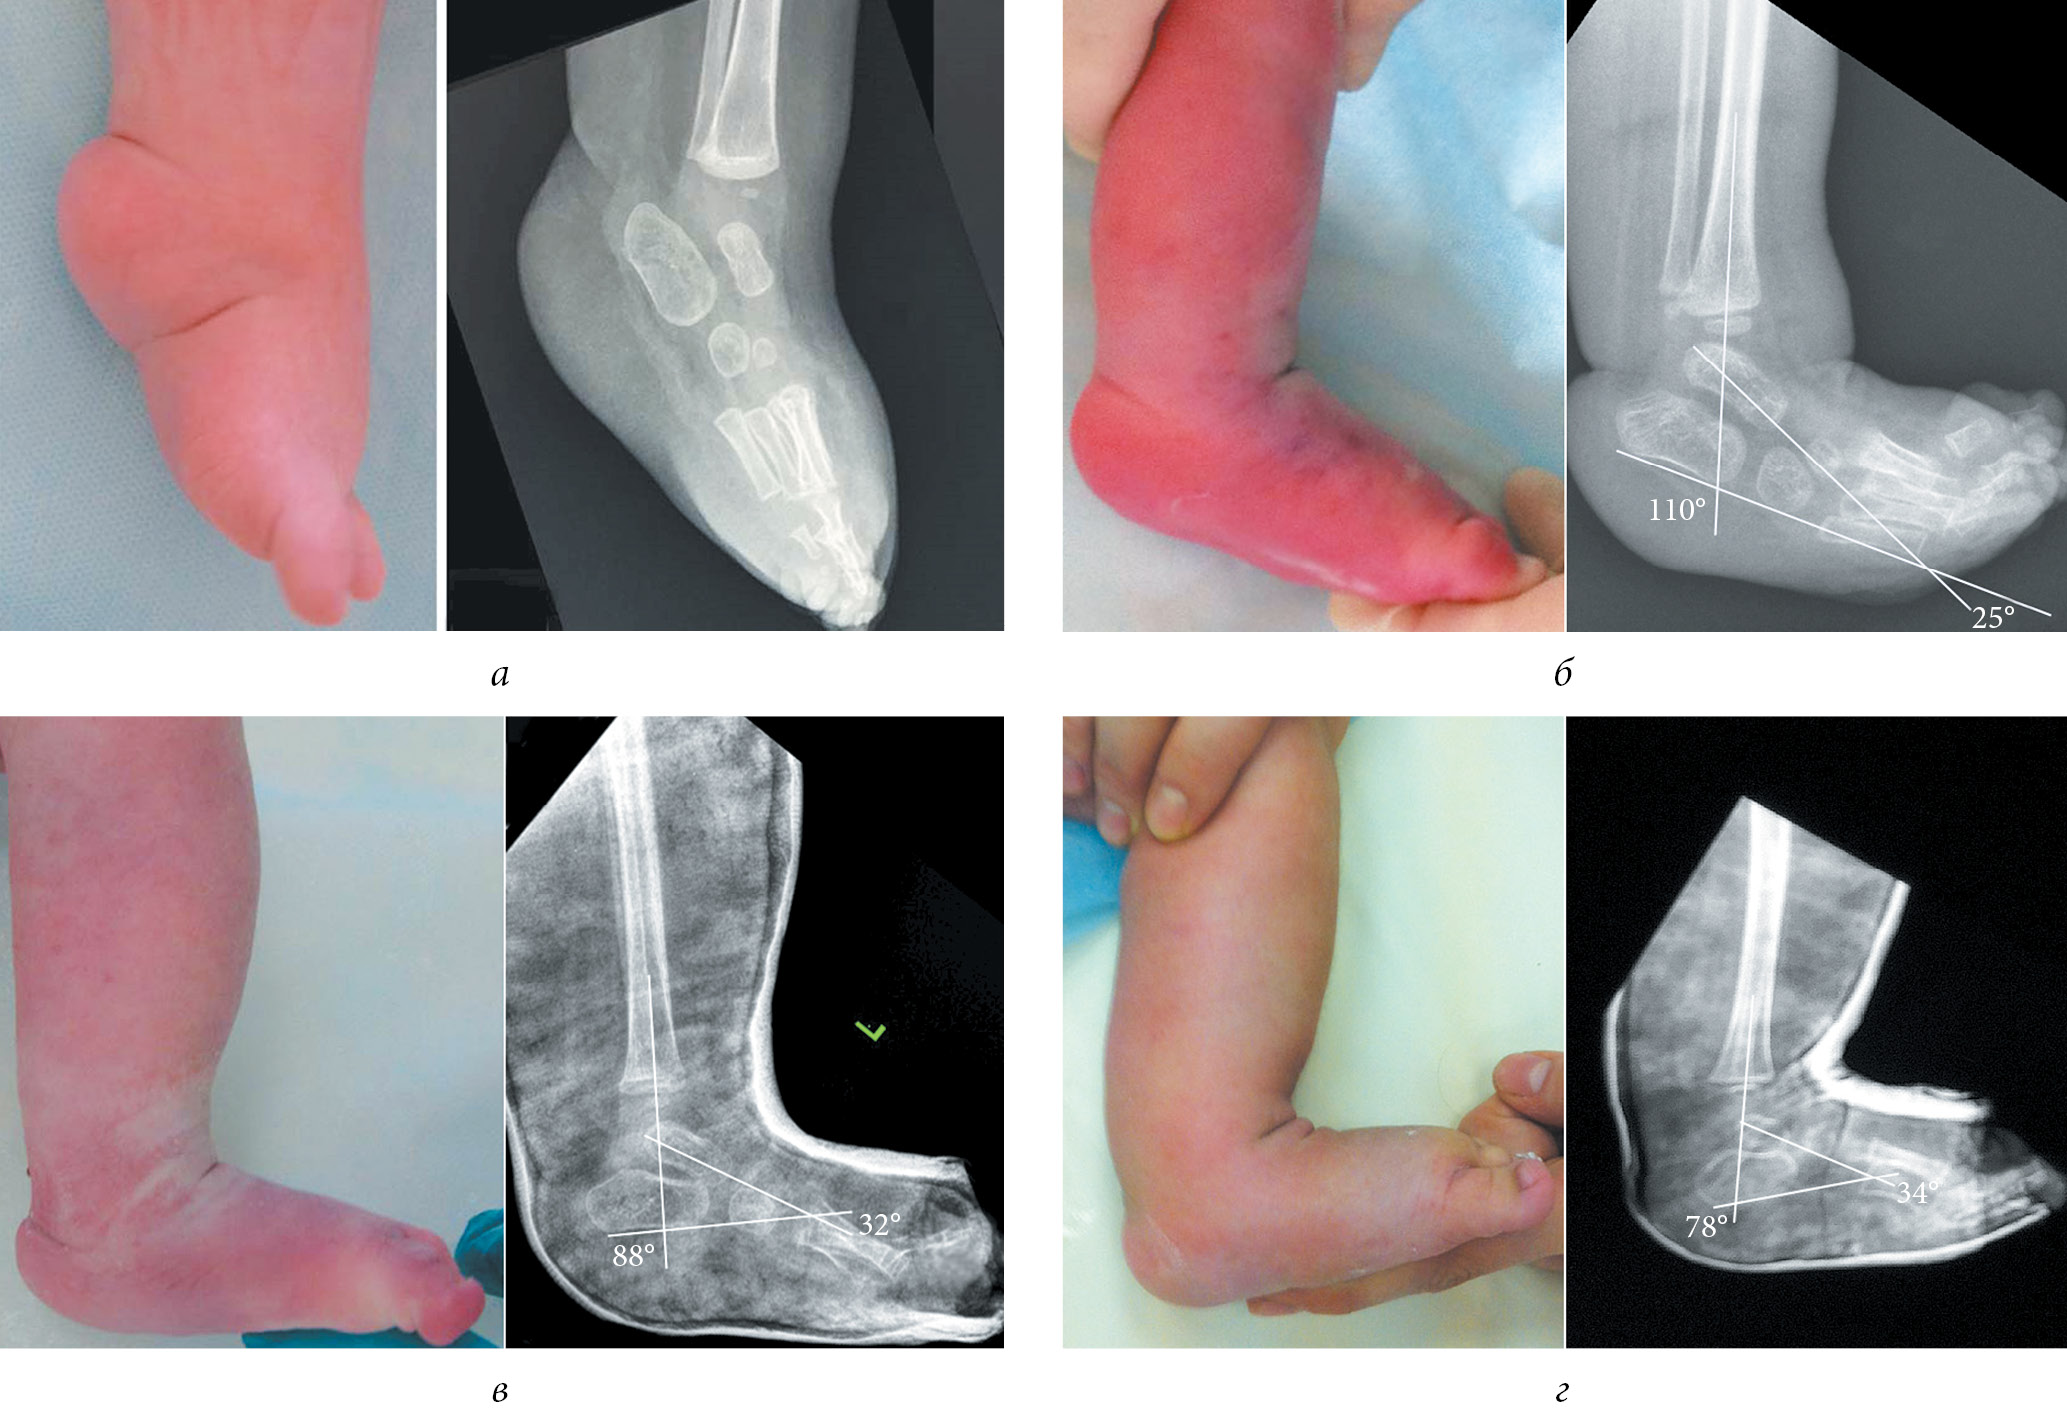

The illustration of some stages of treatment of patients of groups 1 and 2 with clubfoot with arthrogryposis according to the Ponseti method and radiographic data are presented in Figures 2 and 3.

Fig. 3. Appearance and radiograph of the foot in the lateral projection of patient M. with a clubfoot with arthrogryposis from group 2: a — before the beginning of Ponseti method of casting; b — before achillotomy; and c — after achillotomy